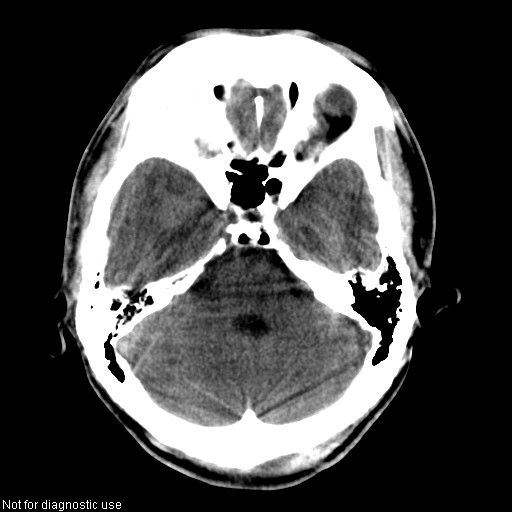

以下是引用hhcckk在2008-1-26 16:03:00的发言:[br]考虑病毒感染可能性大[br]1、病人发病时间短,1周,转移病灶时间长[br]2、楼主虽然没有告诉我们年龄,但从颅内情况来看,病人年纪不会很大,脑池,脑沟不是很明显,当然,可能有脑肿胀的原因,转移灶病人年纪一般较大[br]3、从病灶特点来看,转移多发生在灰白质交界区,多有指状水肿,占位效应明显,此病人呈对称性发布,发生在脑实质深部,与转移有所区别[br]4、病人经抗炎,止咳效果不好,可能是病毒感染,抗生素治疗效果不好[br]5、建议楼主1、增强 2、有呼吸系统的症状何不拍个胸片